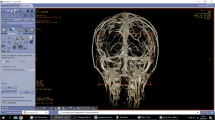

Imaging of the cadaveric specimens was performed with the Artis Q biplane system (Siemens Healthineers, Erlangen, Germany). High-resolution plain radiographs in standard and oblique views and cone-beam CTs (DynaCT) with various field of views (22 and 48 cm) were performed. Cone-beam CT parameters were 20 s acquisition time, 0.4° increment, and 496 total projections. Post-processing was performed by a senior interventional neuroradiologist on a dedicated workstation (Leonardo, Siemens Healthineers) using various kernels to create secondary reconstructions with smaller volumes of interest (VOI). Data were presented as multiplanar reconstructions (MPR), maximum intensity projections (MIP) and with volume rendering technique (VRT). Reading of images was done simultaneously by a neuroradiologist and a neurosurgeon while dissecting the specimens. Images were analyzed via cross-referencing venograms and cadaver dissection via visual cues based on anatomic understanding as illustrated in Fig. 3b, c.

For each cadaver head, radiographic images of both the superficial and the deep venous systems of the brain showed filling of veins down to 150 \(\mathrm{\mu m}\) in diameter (Fig. 3a, b). With the optimized injection technique, the heads had a more homogenous cast allowing better discrimination between vascular structures and brain tissue during dissection. The venous anatomy in the quadrigeminal cistern was chosen as the area of reference among the seven scanned and dissected heads. We managed to identify both larger vessels and sinuses and smaller vessels and tributaries on parallel dissection images and 3D reconstructions as shown in Fig. 3b, c. During dissection, the brain preparation allowed realistic retraction and manipulation during microsurgical instrumentation and was found to be a suitable model to practice neurosurgical approaches. Dissections carried out more than 6 months after cadaver preparation and injection had these qualities preserved.

a Lateral projection of a cadaveric head injected with a 25% latex-barium mixture into the internal jugular veins. High-resolution visualization of the Galenic system and posterior fossa veins. b Volume rendering technique (VRT) after cone-beam CT showing the same anatomy in 3D with significantly more details. c Surgical dissection of the same specimen showing the same anatomy in posterior view. Arterial injection was done with red latex and no barium